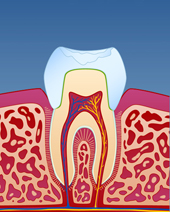

figur IV

Bildet viser et eksempel på alvorlig tanngnissing.